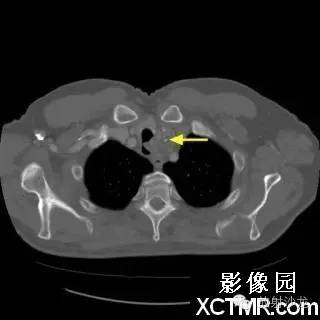

On the contrast-enhanced CT of the chest, there is a heterogeneous mass arising from the left lateral wall of the trachea. The mass demonstrates extratracheal extension as well as extension into the tracheal lumen. (Figure 1 and Figure 2). The mass also contains internal calcifications (arrows), representing chondroid matrix mineralization (Figure 3 and Figure 4).

胸部增强扫描示气管左侧壁发出一不均质的肿块影,肿块向气管内外扩展(图1、2)。其内可见钙化影(箭头),代表软骨基质的钙化(图3、4)。